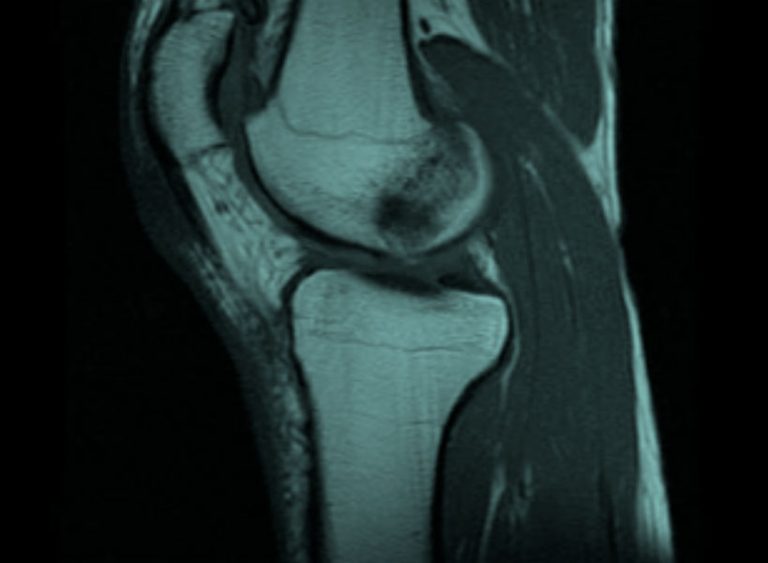

Tratamiento del edema óseo en los huesos del pie o tobillo CIRUGIA

Edema Oseo En Tobillo. hinchados hinchan hematology